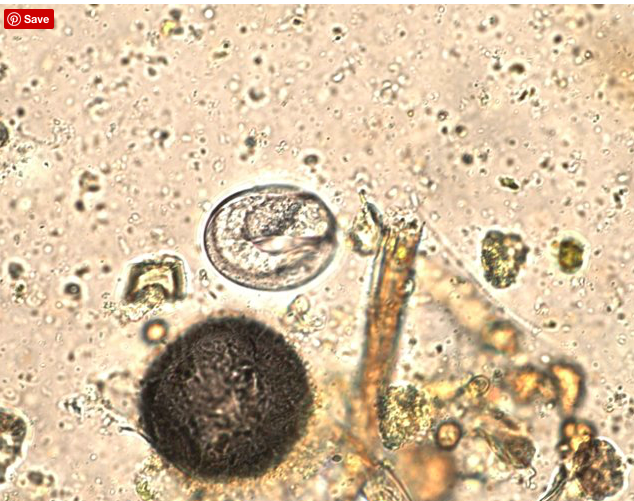

What is this and how would you treat it?

Colic with an associated painful mass at the root of the mesenery is suspicious for verminous arteritis caused by damage to the cranial mesenteric artery and its branches by Strongylus vulgaris. The strongyle egg shown in the picture confirms the cause in this question. A number of anthelmintics are effective including benzimidazoles, pyrantel and ivermectin.